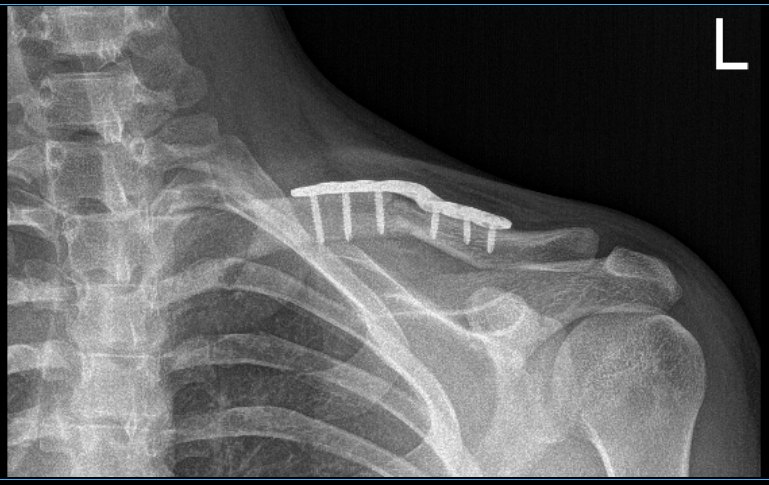

With sharp and blunt dissection, the bone and the fracture site were reached and exposed. The fracture site was opened up and washed and cleaned with curette. The fracture was reduced and a superior plate was put. The plate was fixed proximally and medially with two screws process for lagging for compression.

Finally, the plate was put and compression was done using a compression screw. Two nonlocking g and one locking screw were used on either side. The final images were taken and found to be satisfactory. Final images were saved.

The patient was extubated and moved to the postoperative recovery unit in a stable condition. After two weeks, the patient checked in, with presented XR, and no periprosthetic lucency. The sternoclavicular joint demonstrates normal alignment.

4 weeks X-ray results of left clavicle after surgery

12 weeks X-ray results of left clavicle after surgery

14 weeks X-ray results of left clavicle after surgery